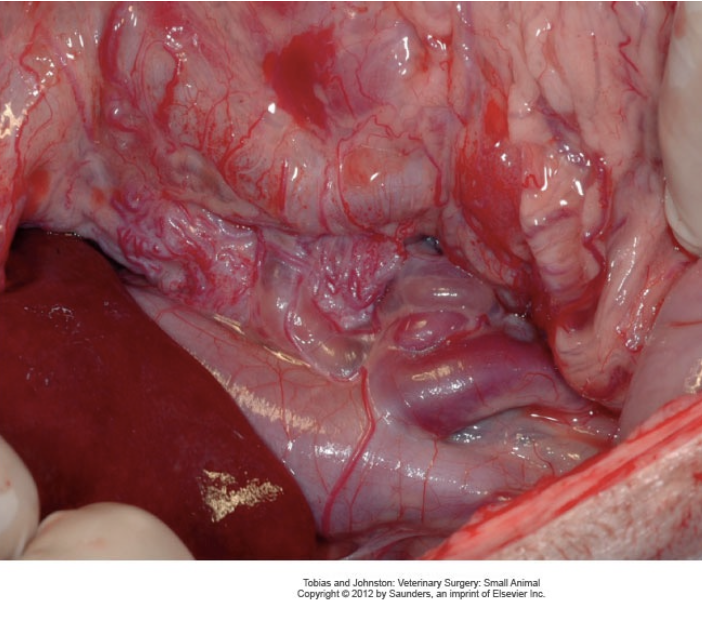

What are the types of portosystemic shunts?

- Congenital: Direct communication with the portal venous system and systemic circulation (bypasses liver) which are commonly single and can be intra- or extrahepatic

- Acquired: Secondary to chronic portal hypertension which are more commonly multiple, torturous and extrahepatic

Describe the differences between extrahepatic and intrahepatic congenital PSS.

- Extrahepatic: 2/3 of PSS, more common in small breeds

- Intrahepatic: More common in large breeds with a larger volume of portal blood being shunted resulting in more severe clinical signs